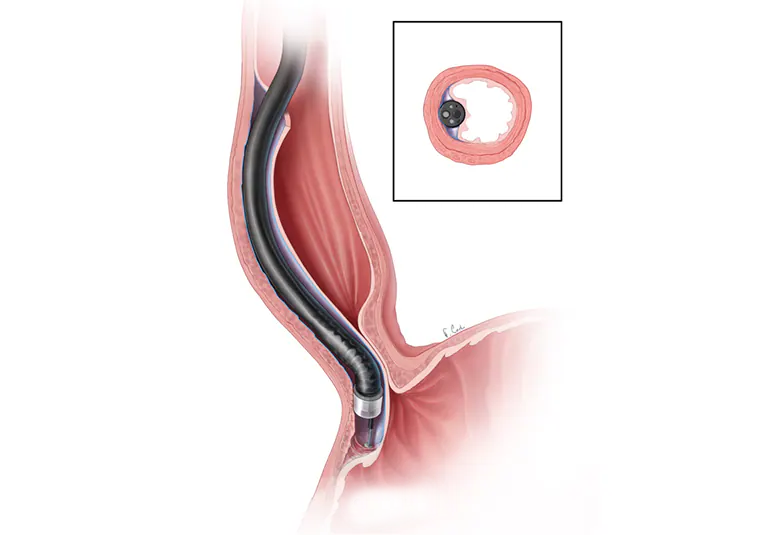

A specialized procedure used to diagnose and treat disorders of the bile ducts and pancreas. Common indications include: